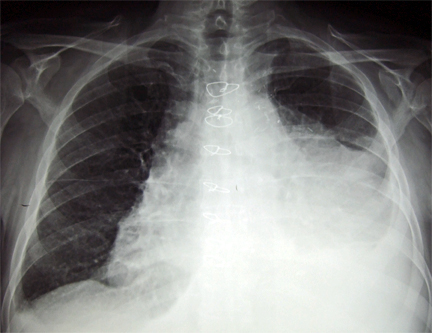

- Radiografia de tórax: tipicamente normal, mas nos casos em que cursam com derrame pericárdico, pode ser visto silhueta cardíaca aumentada com campos pulmonares claros.